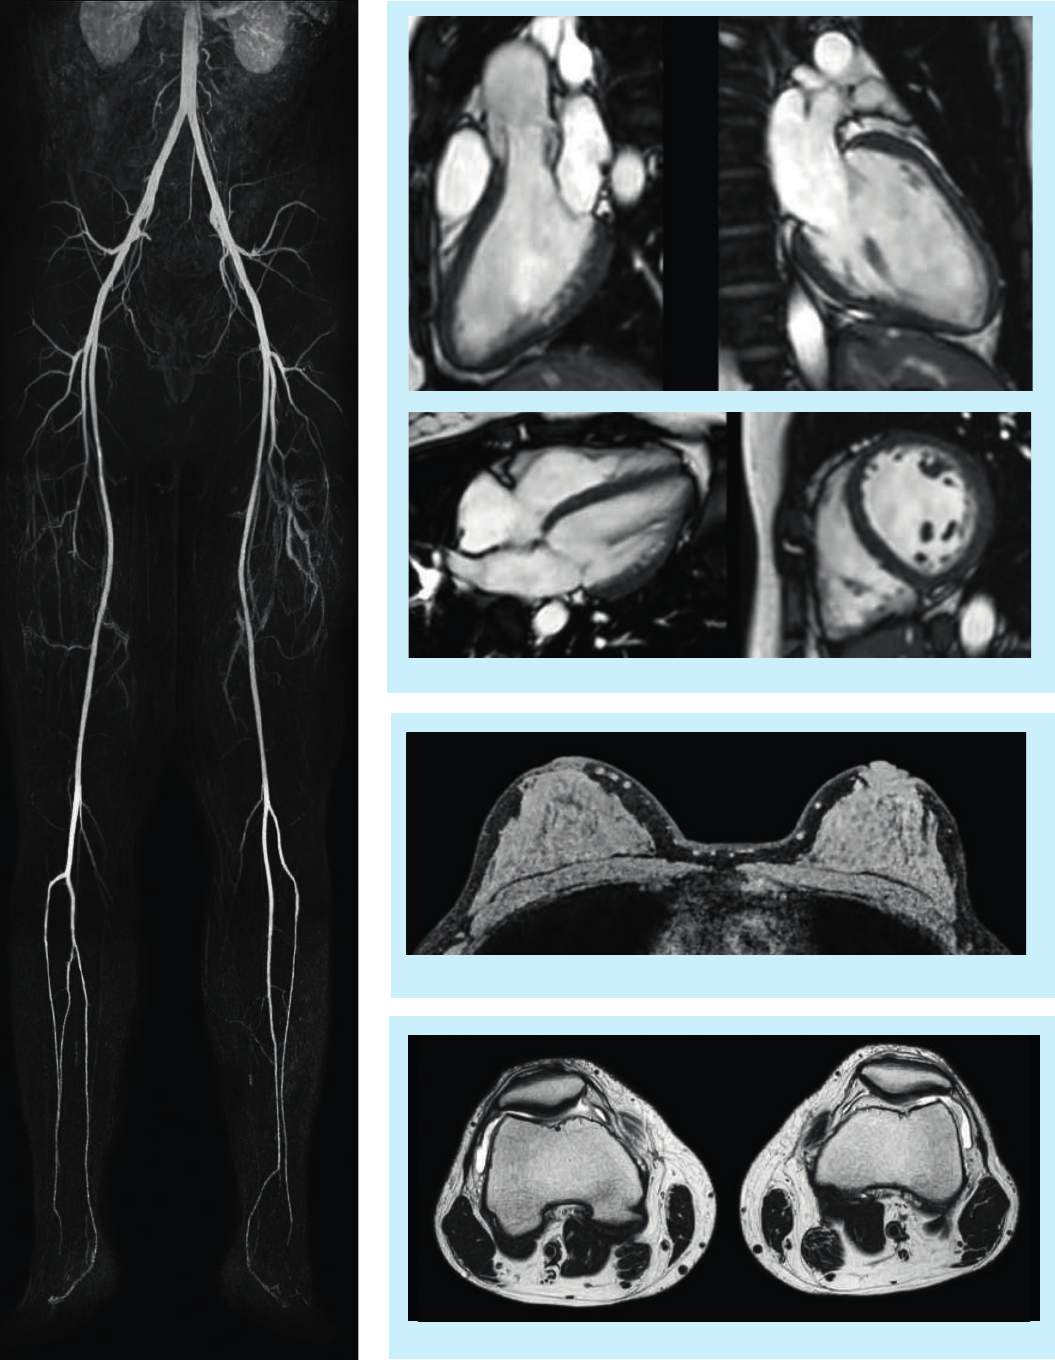

High resolution eTHRIVE with dS-SENSE factor 9

Cine imaging of the heart

T2W imaging of both knees using dS Torso

Peripheral MRA

New solutions for emerging applications

In addition to the growth in traditional applications of MR, there is an increasing role for MR in

oncology and cardiology applications. Designed to address these trends, Ingenia 1.5T provides

advanced functionality for oncology and cardiac applications, safeguarding your investment.

Differentiate your practice with oncology imaging

As MR continues to demonstrate value in cancer

imaging, staging, treatment planning and monitoring,

offering oncology services is of growing interest.

The Ingenia 1.5T positions your practice to provide

outstanding oncology services.

Ingenia 1.5T advantages:

•The accuracy provided by the magnet’s high

homogeneity, combined with the exceptional linearity

of the gradient coil, makes it ideally suited to address

diagnostics through therapy planning.

•Fusion of anatomical and diffusion data delivers robust

and sensitive results in a timeframe comparable to

the gold standard PET-CT exam, bringing whole

body oncology staging and follow-up to the clinical

mainstream.

•The ultra-large FOV with 70 cm bore can facilitate

imaging in the treatment position for possible future

radiation therapy applications.

•FlexTrak Mammo, a dockable patient support and on-

console breast biopsy planning system, allows seamless

integration of breast MR into your department.

3D T2W VISTA Breast

High quality multi-station body DWI

Cardiac imaging made easy

Ingenia 1.5T with dStream and Elite Cardiac Clinical

Solutions advances cardiac MR workflow to mainstream

use.

•Powerful clinical tools such as kT-BLAST, PSIR, and

volumetric imaging for cutting edge, one-stop cardiac

MR exams.

•Supporting dStream coil solution and wireless VCG for

high quality cardiac imaging.

•Workflow support tools such as Real Time interactive

planning and Cardiac Explorer for task-guided

processing including automated segmentation, screen

layout and reporting.

Quantitative flow analysis of the aorta

Black Blood cardiac imaging with and without fat

suppression

Fast whole body

T2W imaging